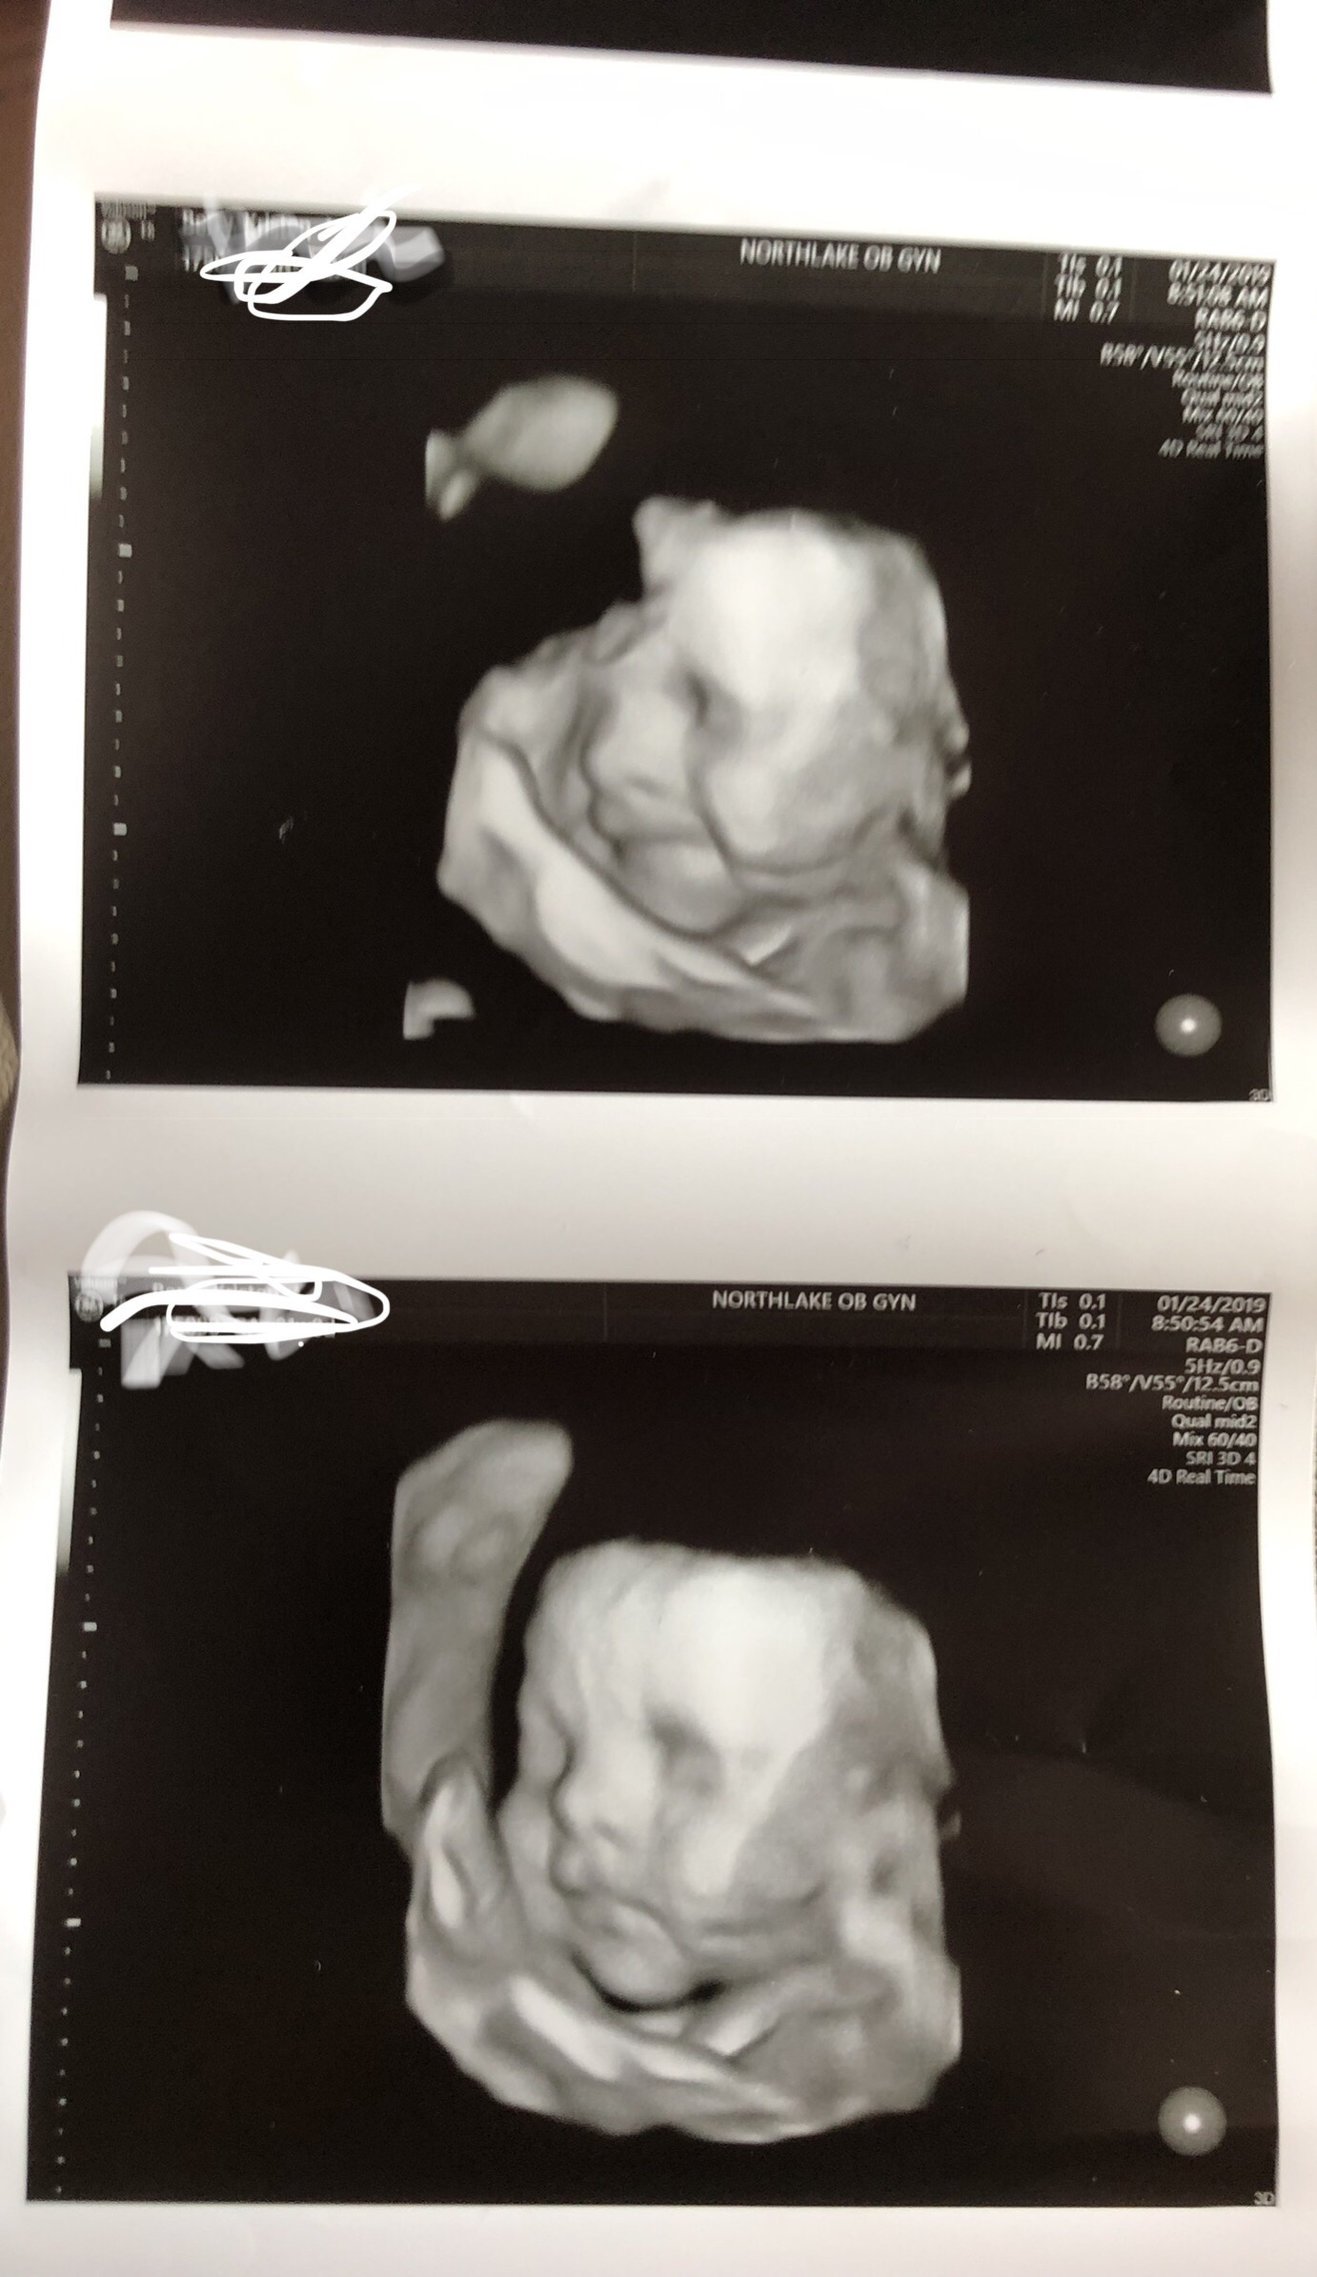

I love the late 3d scans! It is really a sneak peek of baby! The tech at one of my first BPP at 32 weeks did a quick 3d scan just for us to show the face and it really did look like she did when she was born! I don't know why it's so amazing because obv. the scan is seeing the actual baby...but it's sometimes hard to imagine that you have an actual person inside of you.

@kristimh80 what a cutie!! I’ve looked at my 3b a bunch of times trying to guess what this little guy will look like. I compared one of a friend with the actual baby and I definitely saw the resemblance!